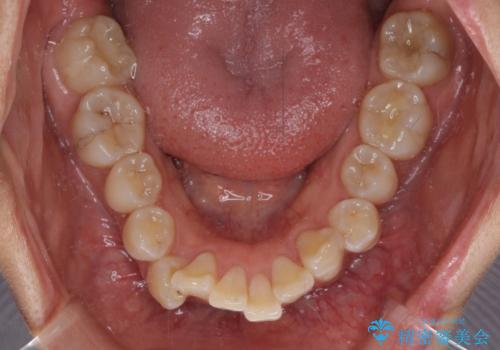

骨格的に上顎歯列が前方位にあり、口元の突出感が顕著な状態で、上下左右の第一小臼歯4本を抜歯して、ワイヤー装置での抜歯矯正を行うこととしました。

奥歯の咬み合わせ改善のために、アンカースクリューの使用と上顎左右第一小臼歯の抜歯のタイミングをコントロールして、理想的な咬み合わせに仕上げていくこととしました。

ご本人がびっくりするくらい劇的に口元の突出感が改善され、大変満足のいく仕上がりとなりました。